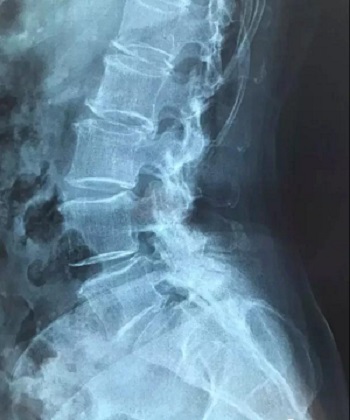

八、拍片子时,如果一张片子上有两张图像的时候,合起来拍一张,分开再各拍一张(如以下三张)